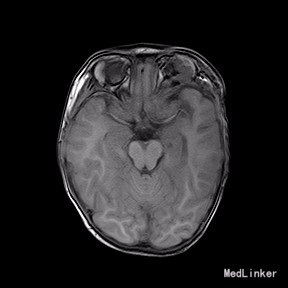

2岁9月患儿,因“左眼睑下垂1年余,头痛、呕吐8天”入院。家属1年前发现患儿左侧眼睑下垂,无法自行张开,一直未予特殊诊治。8天前患者哭闹频繁,诉头痛如爆炸样,剧烈难忍,并出现呕吐胃内容物数次,无伴抽搐、视力下降,无意识障碍。当地医院头颅MRI提示:左侧眼眶扩大,左侧眼球外上方泪腺区见一条状迂曲异常信号影,T1WI呈等信号,T2WI上病灶外缘呈高信号,内为等信号,增强扫描病灶中央呈条状明显强化影,边缘无明显强化,双侧大脑半球对称,灰白质对比正常,未见局灶性信号异常,左侧中颅窝前分蛛网膜下腔增宽,内为脑脊液信号;各脑室、脑池大小、形态均正常,中线结构居中,幕下小脑、脑干无异常,矢状面示垂体大小形态正常,未见局灶性信号异常;增强扫描未见明显异常强化。

完善相关检查,在气管插管麻下行“左额眶部占位病变切除术”。术后病理诊断为“(左眼眶)丛状神经纤维瘤”。术后给予患儿脱水、营养脑神经、抗感染等对症治疗。复查CT未见明显异常。

患儿术后2周左眼睑下垂较术前好转。双侧瞳孔反射、眼球活动均无异常。 丛状神经纤维瘤主要发生于眼睑,在出生后或幼年时期即出现症状和体征。侵袭范围广泛,包括眼睑、眶内软组织、眶骨和邻近的脑、颞部等。眼部最早和最多见为上、下睑软性肥厚,皮下瘤组织增生,使上、下睑隆起。眼睑皮肤常有淡棕色色素斑,眼球向前突出和向下移位。眼球突出虽然很显著,但向眶内纳入并不困难。肿瘤组织可直接侵袭眶内各种结构,上睑提肌首先被波及,引起上睑下垂,上举不足或不能。MRI可准确显示病变的范围尤其显示病变与邻近结构的关系,也可清楚显示其他部位伴发的肿瘤,但难以清晰显示眶壁骨质改变。手术治疗是必要的,手术切除应注意以下问题:1.眼睑病变的切除;2.眶内病变的处理;3.提上睑肌的处理;4.眶骨缺失的处理。丛状型术前诊断容易,但治疗较为棘手,易复发。